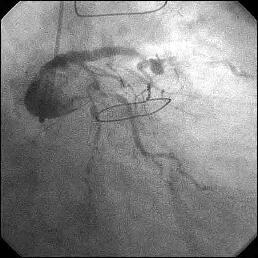

�Ǘ��72�Ώ����Brisk factor��HT, HL, DM�ł��B

��2�T�ԑO�̔��ǂƎv����Recent MI�ł��BLAD#7: total��Tristar3.0�~18?�����

�܂����B

����LCx ostium: 75%�ł��B������PCI���悤�Ǝv���̂ł����A�ǂ̂悤��strategy

���l������ł��傤���H

���Ȃ݂ɓ��@�ł�DCA�g�p�o���҂͂��܂���B

DCA�ł���l��A��Ă���A�Ƃ����I�������܂߂Č䏕��������K���ł��B

�X�������肢���܂��B

|

|

|

|

|

����������������������������������������������������������������������������